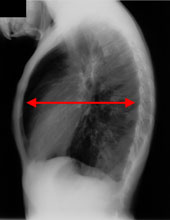

胸部立位側面

同じお子さんの胸部を横から撮影したものです。肺の含気が高まったために、前胸部が飛び出した「樽状胸」と言われる形になっています。